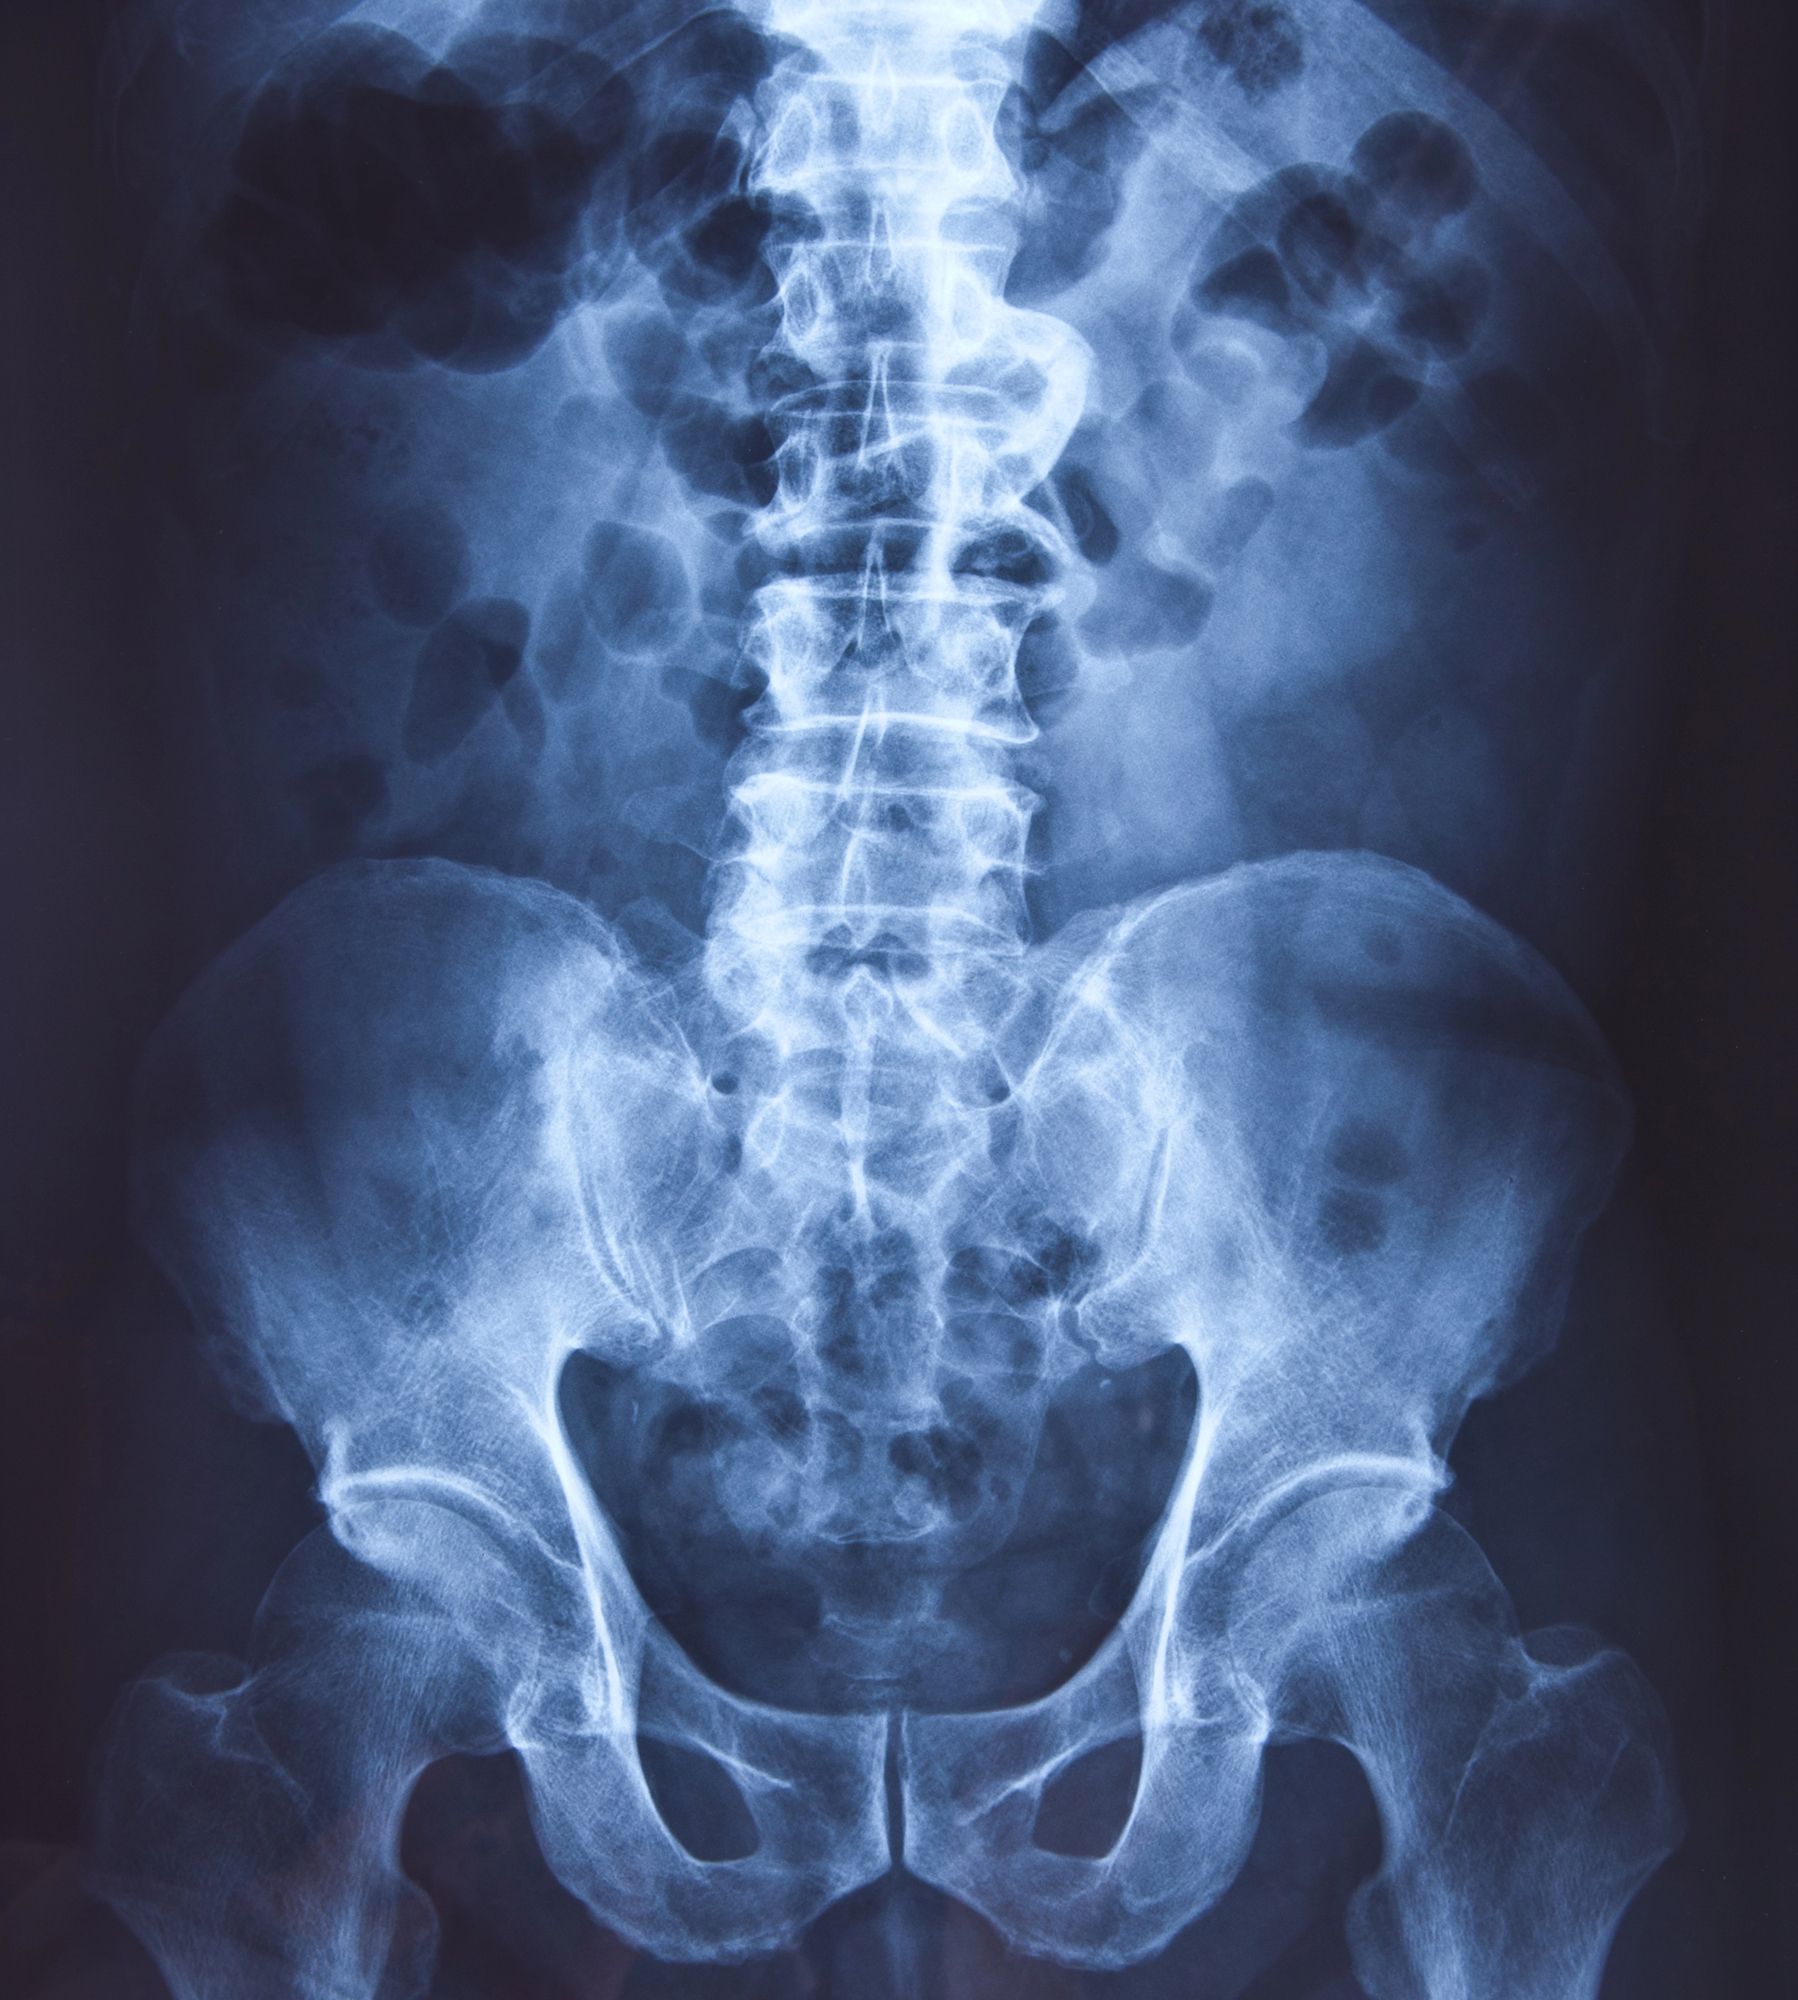

Il pangonogramma è considerato uno degli esami di riferimento nella diagnosi delle alterazioni posturali, poiché consente di osservare il comportamento del bacino, della colonna lombare, delle ginocchia e delle caviglie sotto il peso del corpo. L’immagine radiografica ottenuta mostra il modo in cui le strutture scheletriche si allineano quando il paziente si trova in posizione naturale, elemento fondamentale per studiare eventuali compensi, deviazioni o sovraccarichi articolari.

L’esame risulta utile in presenza di dolori lombari ricorrenti, disturbi del cammino o difficoltà nel mantenere una postura equilibrata. La possibilità di confrontare la postura in appoggio monopodalico e bipodalico permette di verificare come varia la distribuzione del carico e di individuare, ad esempio, instabilità del bacino o cedimenti articolari. Nell’ambito del

Pangonogramma mono bi-podalico

vengono valorizzati parametri fondamentali per comprendere la biomeccanica individuale, favorendo una lettura chiara e dettagliata delle strutture coinvolte.

Uno degli aspetti principali valutati attraverso il pangonogramma è la dismetria degli arti inferiori, ovvero la differenza nella lunghezza delle gambe. Anche variazioni minime tra un arto e l’altro possono generare inclinazioni del bacino, sovraccarichi funzionali e modificazioni della postura globale. L’esame consente di osservare come questa differenza, se presente, si manifesta sotto il peso corporeo, fornendo informazioni indispensabili per l’elaborazione di eventuali correzioni posturali o per la programmazione di trattamenti fisioterapici. Oltre alla dismetria, la valutazione comprende l’esame dell’allineamento del bacino, che può risultare inclinato o ruotato, e della stabilità delle principali articolazioni degli arti inferiori.

Pangonogramma mono bi-podalico a Casarano (LE) permette così di ottenere un quadro completo e funzionale del comportamento dello scheletro, elemento fondamentale nelle diagnosi ortopediche e nella pianificazione di percorsi riabilitativi mirati. L’interpretazione radiologica aiuta a riconoscere eventuali asimmetrie della colonna lombare, deviazioni assiali delle ginocchia o alterazioni del carico a livello delle caviglie.